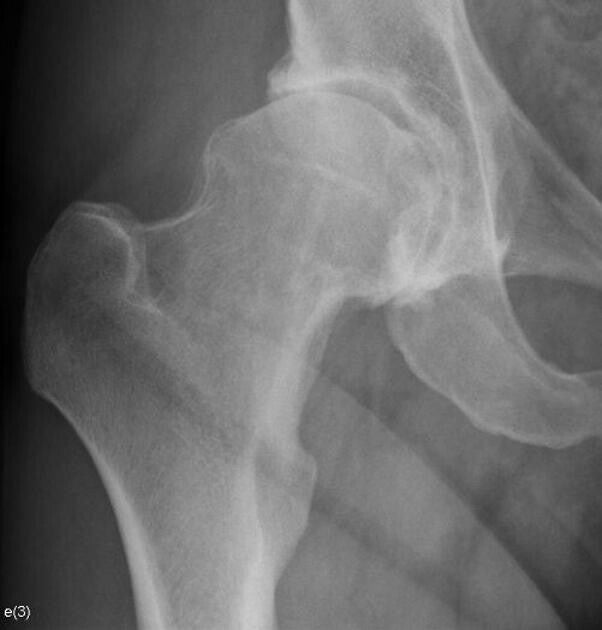

Bij de totale heupprothese-operatie wordt de versleten heup vervangen door een kunstgewricht.

Versleten heup